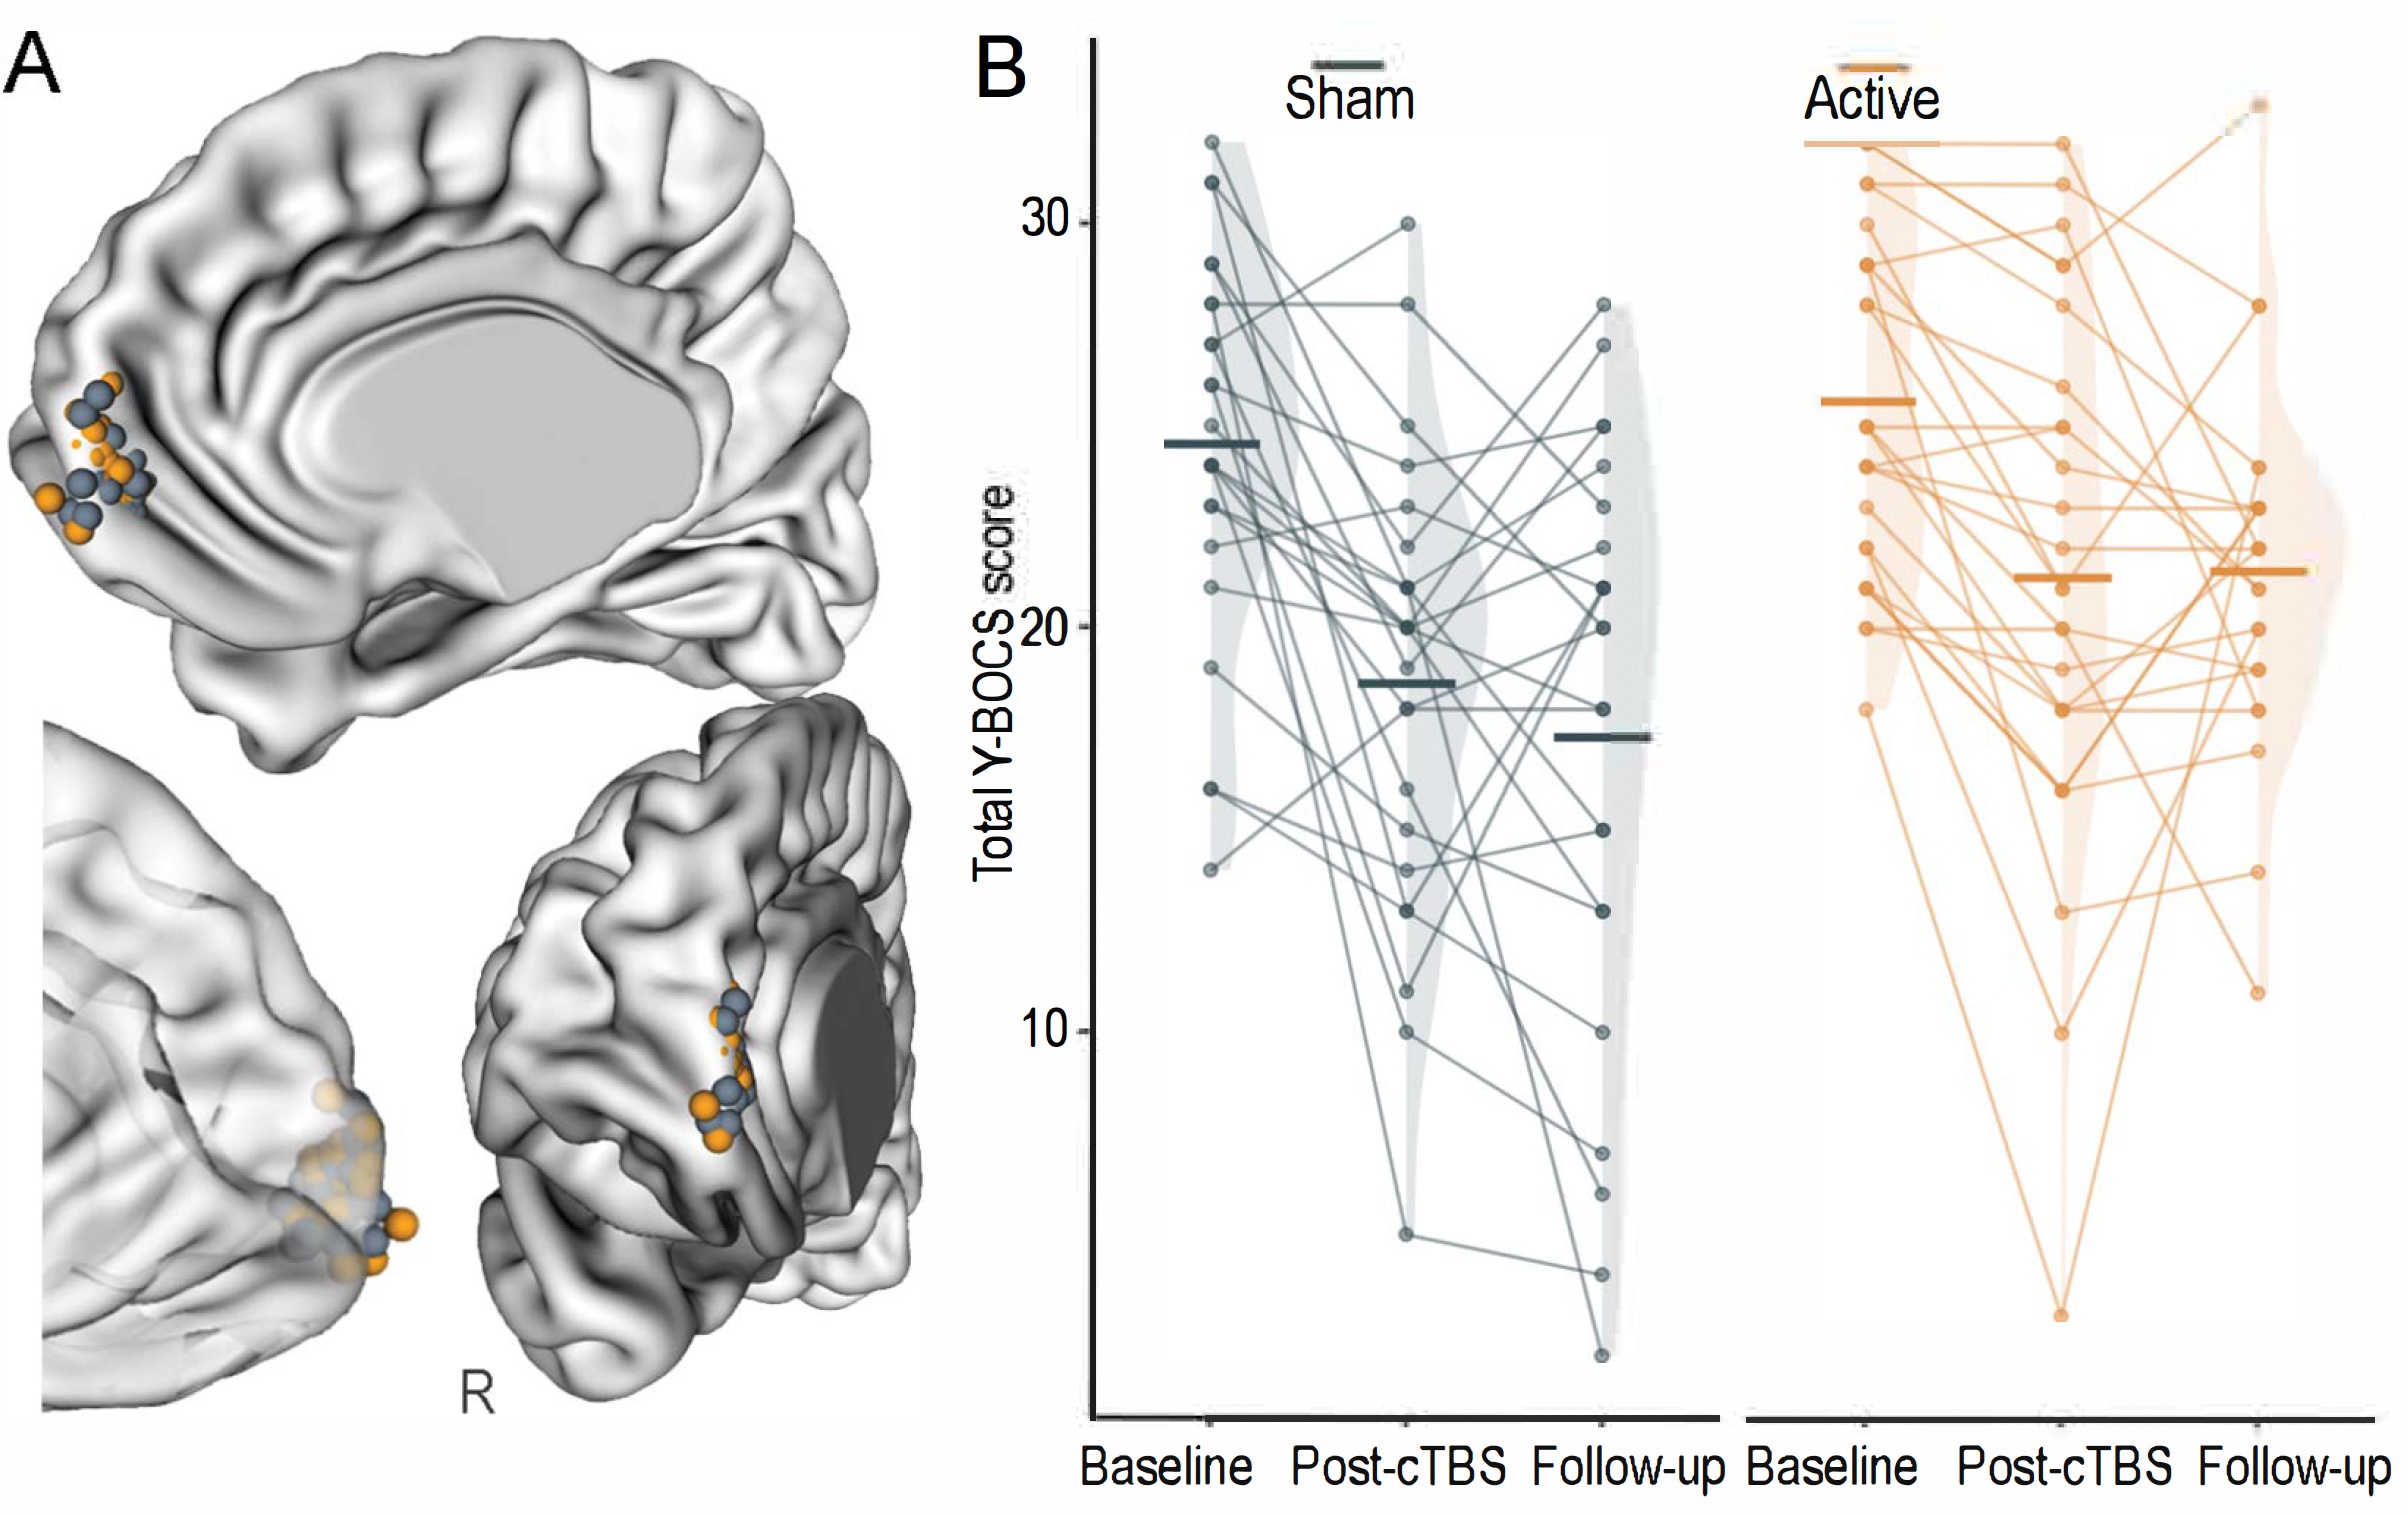

Data engineering, analysis of multimodal dataset, and multiscale modeling of neurostimulation in obsessive-compulsive disorders.